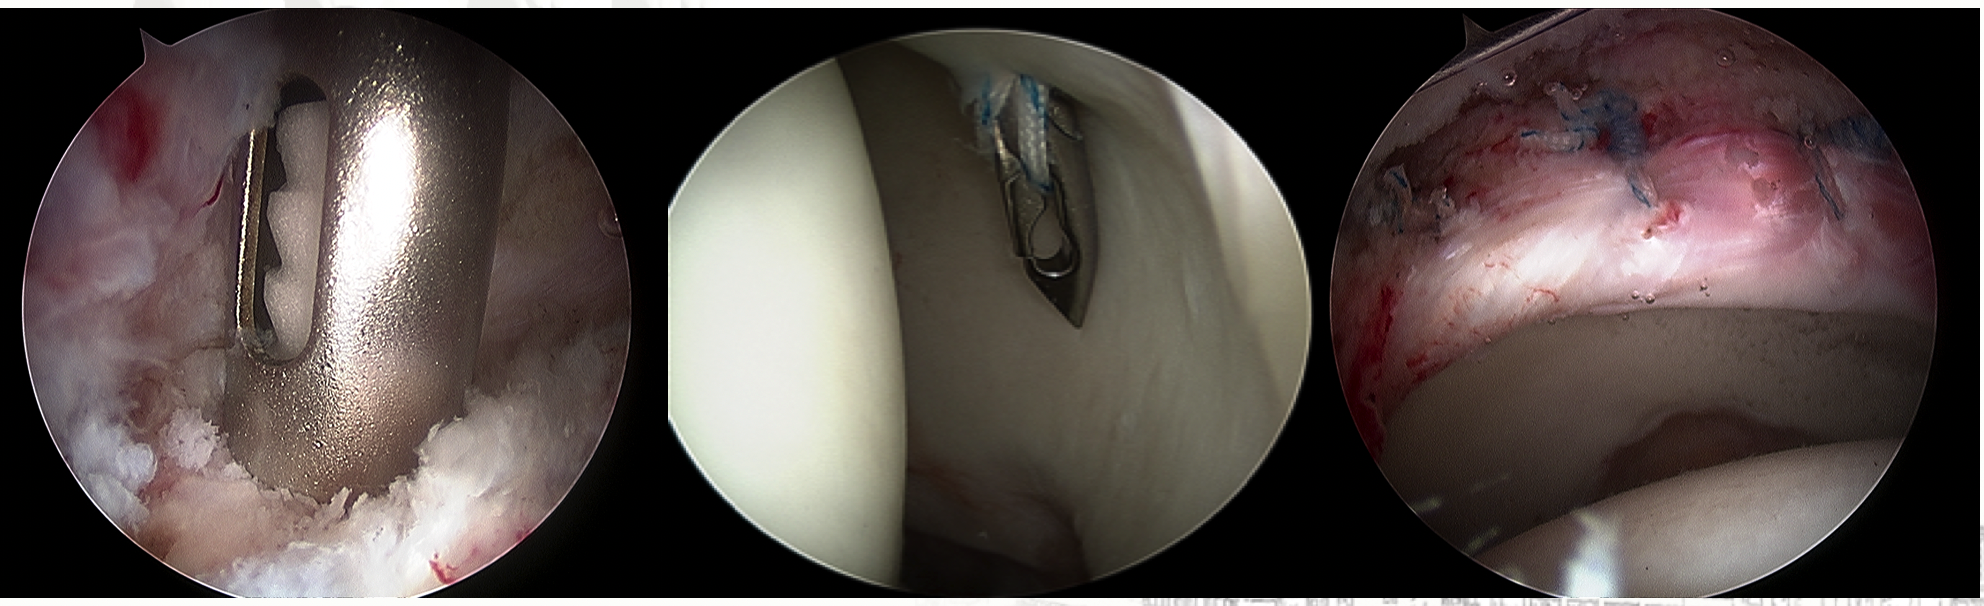

髋关节镜下钙化性肌腱炎的处理